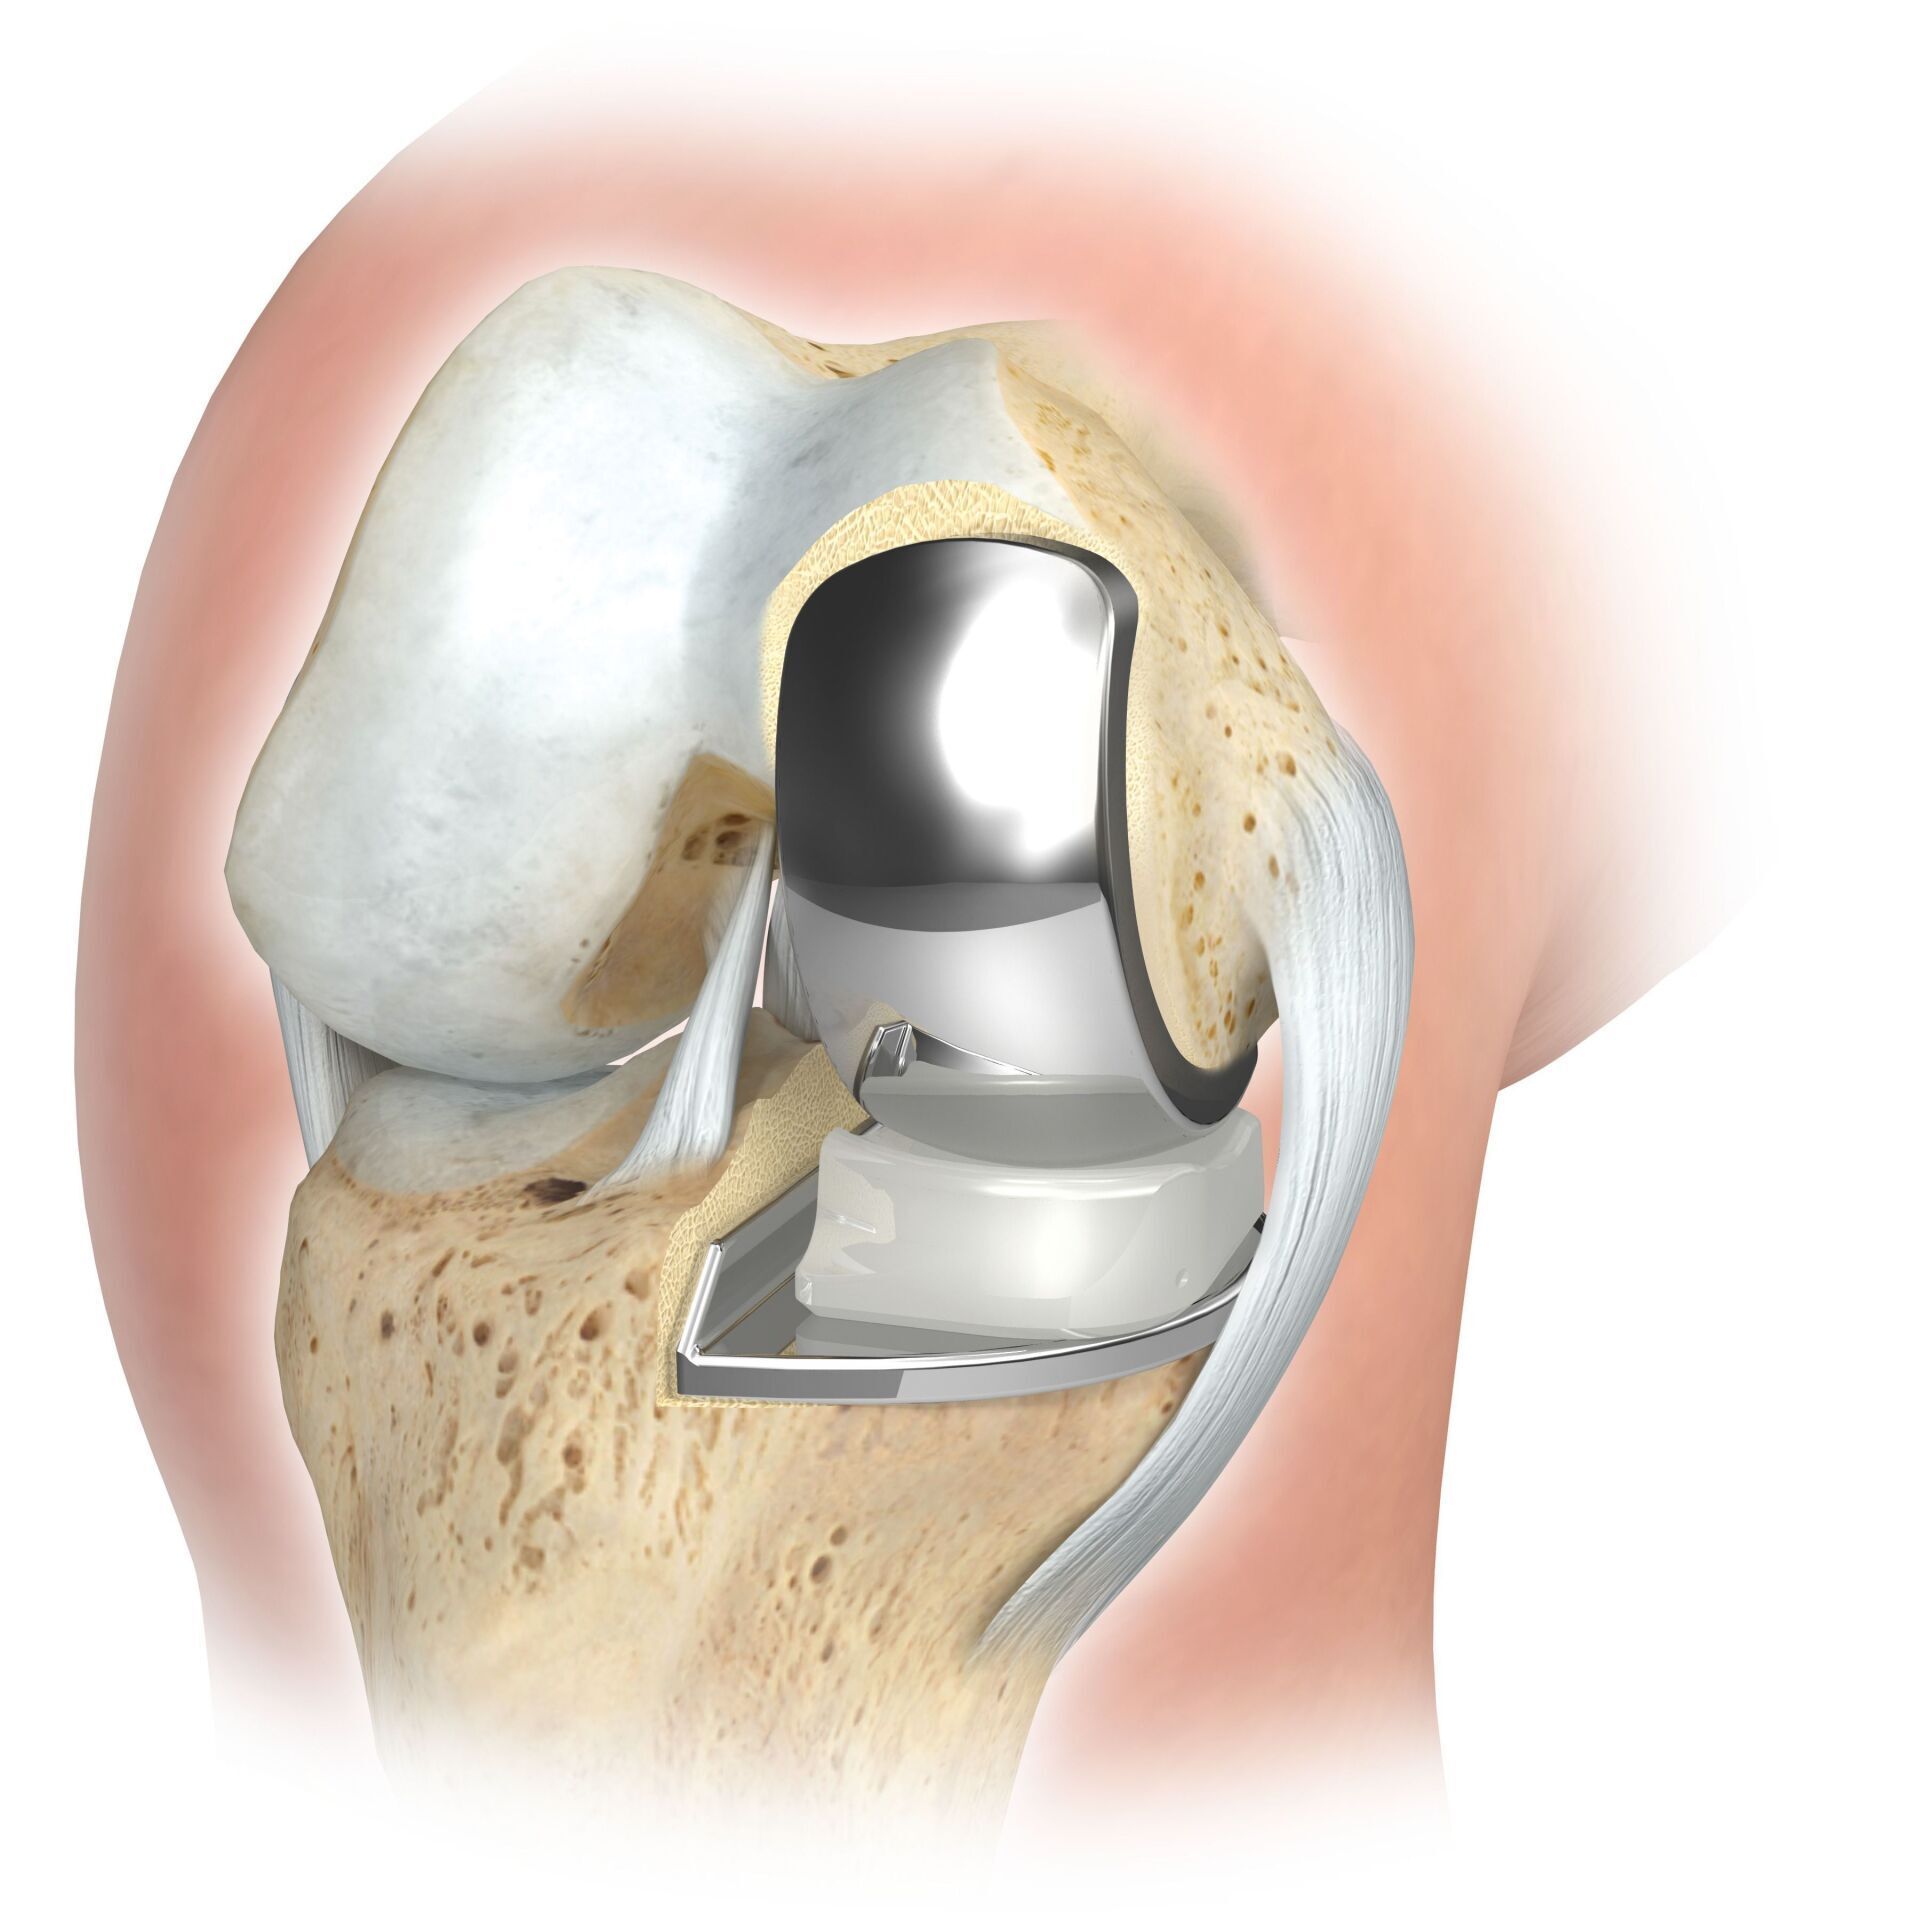

بدلة الشريحة

من الممكن استبدال المفصل الجزئي لمفصل الركبة في جميع مناطق المفصل، ولكن يتم إجراؤه غالبًا في الجزء الداخلي من مفصل الركبة وغالبًا ما يشار إليه بالعامية باسم بدلة الزلاجة. على غرار طقم الأسنان الكامل، يتم استبدال الغضروف المعيب بسطح جديد ويتم إدخال بطانة بلاستيكية بينهما. بالنسبة للطرف الاصطناعي الجزئي، يجب أن تكون جميع هياكل الأربطة، وخاصة الأربطة الصليبية، سليمة إلى حد كبير.